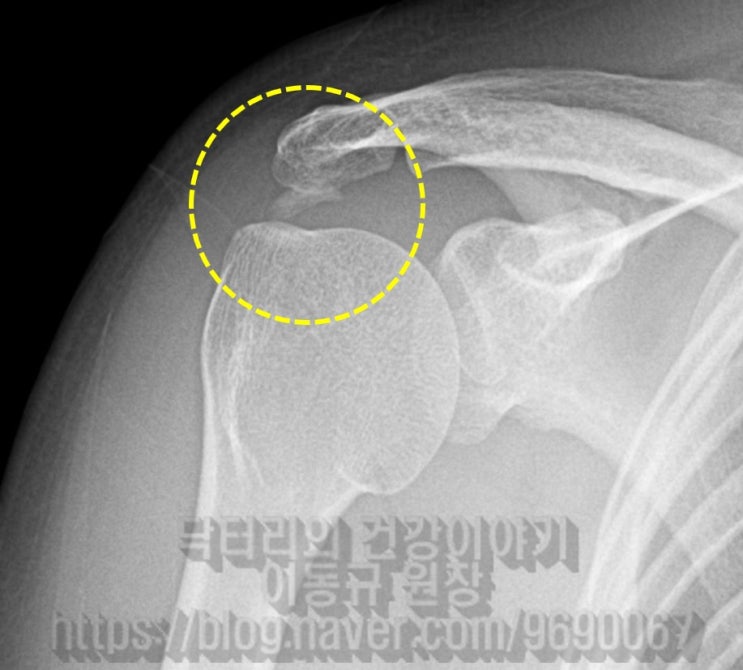

거대한 석회성 건염에서 관절경을 통한 석회 제거술 및 극상근 봉합술(side to side)

43에 여자 환자로 우측 어깨의 극심한 통증을 주소로 내원하였다. 환자는 내원 일주일 전부터 극심한 통증...